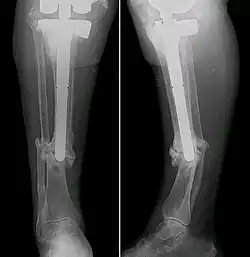

Ilizarov fixation is an effective surgical approach for treating CPT, particularly when significant bone gaps or deformities are present. The technique involves applying an external fixator framework known as an Ilizarov apparatus. Composed of rings connected by wires and thin wires or half-pins inserted into the bone, the apparatus allows precise control over bone alignment by gradually distracting or compressing bone ends.[24] Through application of regulated forces, the Ilizarov method stimulates new bone formation and facilitates bone union. Steady adjustments to the frame can progressively correct deformities, lengthen the bone, and induce consolidation across the pseudarthrosis site.[25] This technique has been proven to have high healing rate and a low refracture rate later on in clinical practice.[26][25]

The Sofield fragmentation technique entails making numerous small bone fractures via controlled osteotomies (surgical bone cuts) in the affected region. Orthopaedic surgeons then stabilize and compress the resultant bone fragments securely using internal fixation devices like plates, screws or intramedullary rods. By intentionally fracturing the bone in a regulated manner and ensuring stability, Sofield fragmentation promotes healing while also assisting consolidation at the pseudarthrosis site.[27][24]

Intramedullary stabilization involves inserting a rod or nail into the tibial medullary canal. This offers structural support from within the affected bone, allowing for bone alignment and union. Surgeons may opt for flexible or rigid intramedullary nails depending on patient-specific factors such as age, pseudarthrosis severity and any accompanying deformities.[28] Although it almost guaranteed fracture healing and no refractures within a few years, the intramedullary nails would need to be replaced with age, leading to the pain of repeated surgery.[29][30][31]

In cases of extensive tibial bone loss or compromised blood flow, surgeons may perform a free vascularized fibular graft. This involves harvesting a section of fibula (usually 10–12 cm long) along with its blood supply from the patient's leg and transplanting it to the pseudarthrosis site.[32] As a vascularized graft, the fibula provides a fresh blood source to aid bone growth and repair at the defect location.[33] This unconventional procedure is reserved for the most challenging clinical presentations, saving many children with CPT from amputation since it was invented in the 1990s.[34] However, due to the lack of mechanical support, the healed bone has a high chance of refracture if this technique was applied alone for CPT treatment.[35] Therefore, it is commonly applied together with intramedullary nails in recent years so as to deal with both tibial loss and low bone mechanical strength, and has demonstrated satisfying efficacy in clinical practice.[36][37]